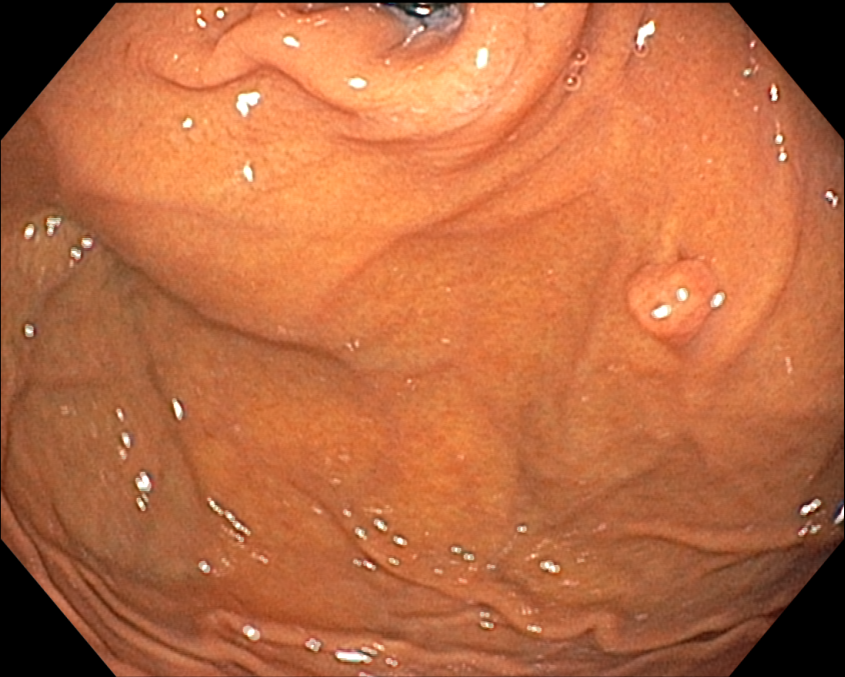

D Fundic gland polyp이고 제거할 필요가 없습니다.

Fundic gland polyp의 악성 잠재성 (malignant potential)은 없습니다. Somatic APC gene mutations이 dysplasia가 없는 syndromic fundic gland polyps의 70 % 이상에서 발견되었으나 sporadic lesions에서는 10 % 미만이었습니다. Sporadic fundic gland polyps과 PPI와 관련된 polyps은 실질적으로 악성 잠재성이 없습니다. 그러나 dysplasia가 드물게 있기도 합니다. FAP 환자의 fundic gland polyps의 경우 30-50%는 dysplasia를 나타내지만 전형적으로는 low grade입니다. 그러나 FAP 환자에서의 adenoma와 대조적으로 fundic gland polyps은 거의 암으로 진행하지 않습니다. Fundic gland polyps은 빈번하게 다발성이고 한 개 이상 대표적인 몇 개의 조직검사로 충분합니다. 남은 polyps은 내시경으로 주의 깊게 (?) 관찰하고 다른 곳과 달라 보이는 polyps은 조직검사를 하고 가능하면 제거합니다. 1 cm 이상의 polyps, 궤양이 있는 poylps, antrum에 있는 polyps은 절제해서 dysplasia는 없는지 neplasia는 없는지 확인해야 합니다. |

Familial polyposis syndrome 가능성은 poyps이 20개 이상인 경우, antrum에 fundic gland polyps이 있는 경우, 젊은 나이 (40세 이전)에 발생한 fundic polyps, 십이지장에 adenoma가 동반된 경우에 고려되어야 하고 대장내시경을 시행해야 합니다. PPI 사용으로 여겨지는 sporadic fundic gland polyps 환자에서 polyps이 20개 이상이거나 1cm보다 큰 경우에는 PPI를 중단합니다. 이와 같은 환자에서 hypergastrinemia는 gastrinoma (Zollinger-Ellison syndrome) 또는 좀 더 일반적으로는 PPI-induced hypochlorhydria를 시사하고 존재한다면 PPI 용량을 줄이거나 중단합니다. 만일 GERD 치료를 위해 위산 분비 억제가 필요하고 H2R blocker로 치료되지 않으면 가장 낮은 용량으로 다른 PPI를 고려합니다. |